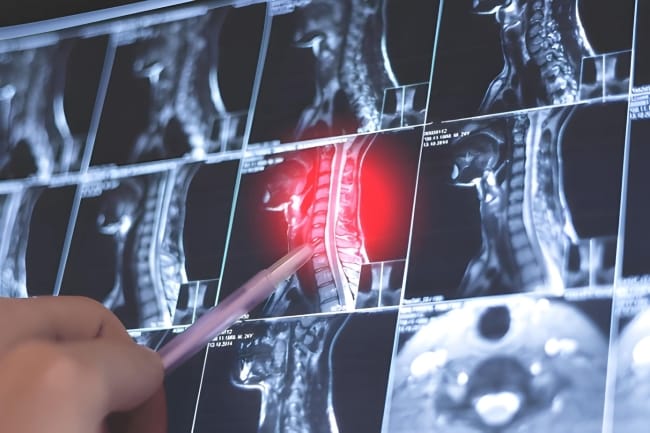

- MRI, untuk melihat kondisi saraf, bantalan tulang, dan jaringan di sekitar tulang leher secara detail

- CT scan, guna mendeteksi adanya penyempitan saluran tempat saraf keluar atau penonjolan bantalan tulang (herniasi diskus)

- Rontgen, untuk menilai struktur tulang leher dan pertumbuhan tulang baru yang mungkin menekan saraf

- Elektromiografi (EMG) dan studi konduksi saraf, guna memeriksa fungsi saraf dan otot serta menentukan lokasi saraf yang terjepit.

Kombinasi hasil wawancara medis, pemeriksaan fisik, dan pemeriksaan penunjang akan membantu dokter memastikan diagnosis cervical radiculopathy dan menentukan pengobatan yang paling tepat.